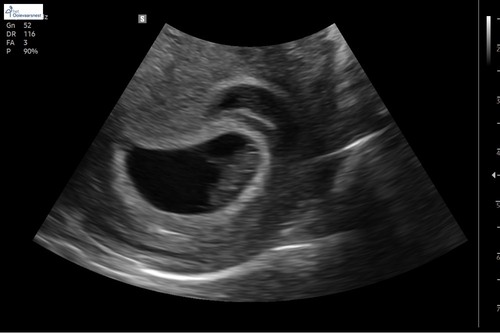

Hier de echo van 7+5 van het zijaanzicht via inwendige echo. Ik kan er niet veel van maken nog 😂😂